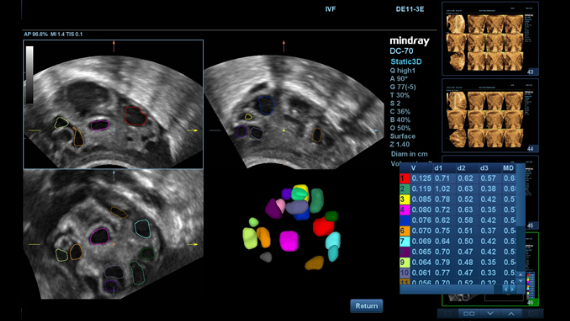

ImĂĄgenes clĂnicas